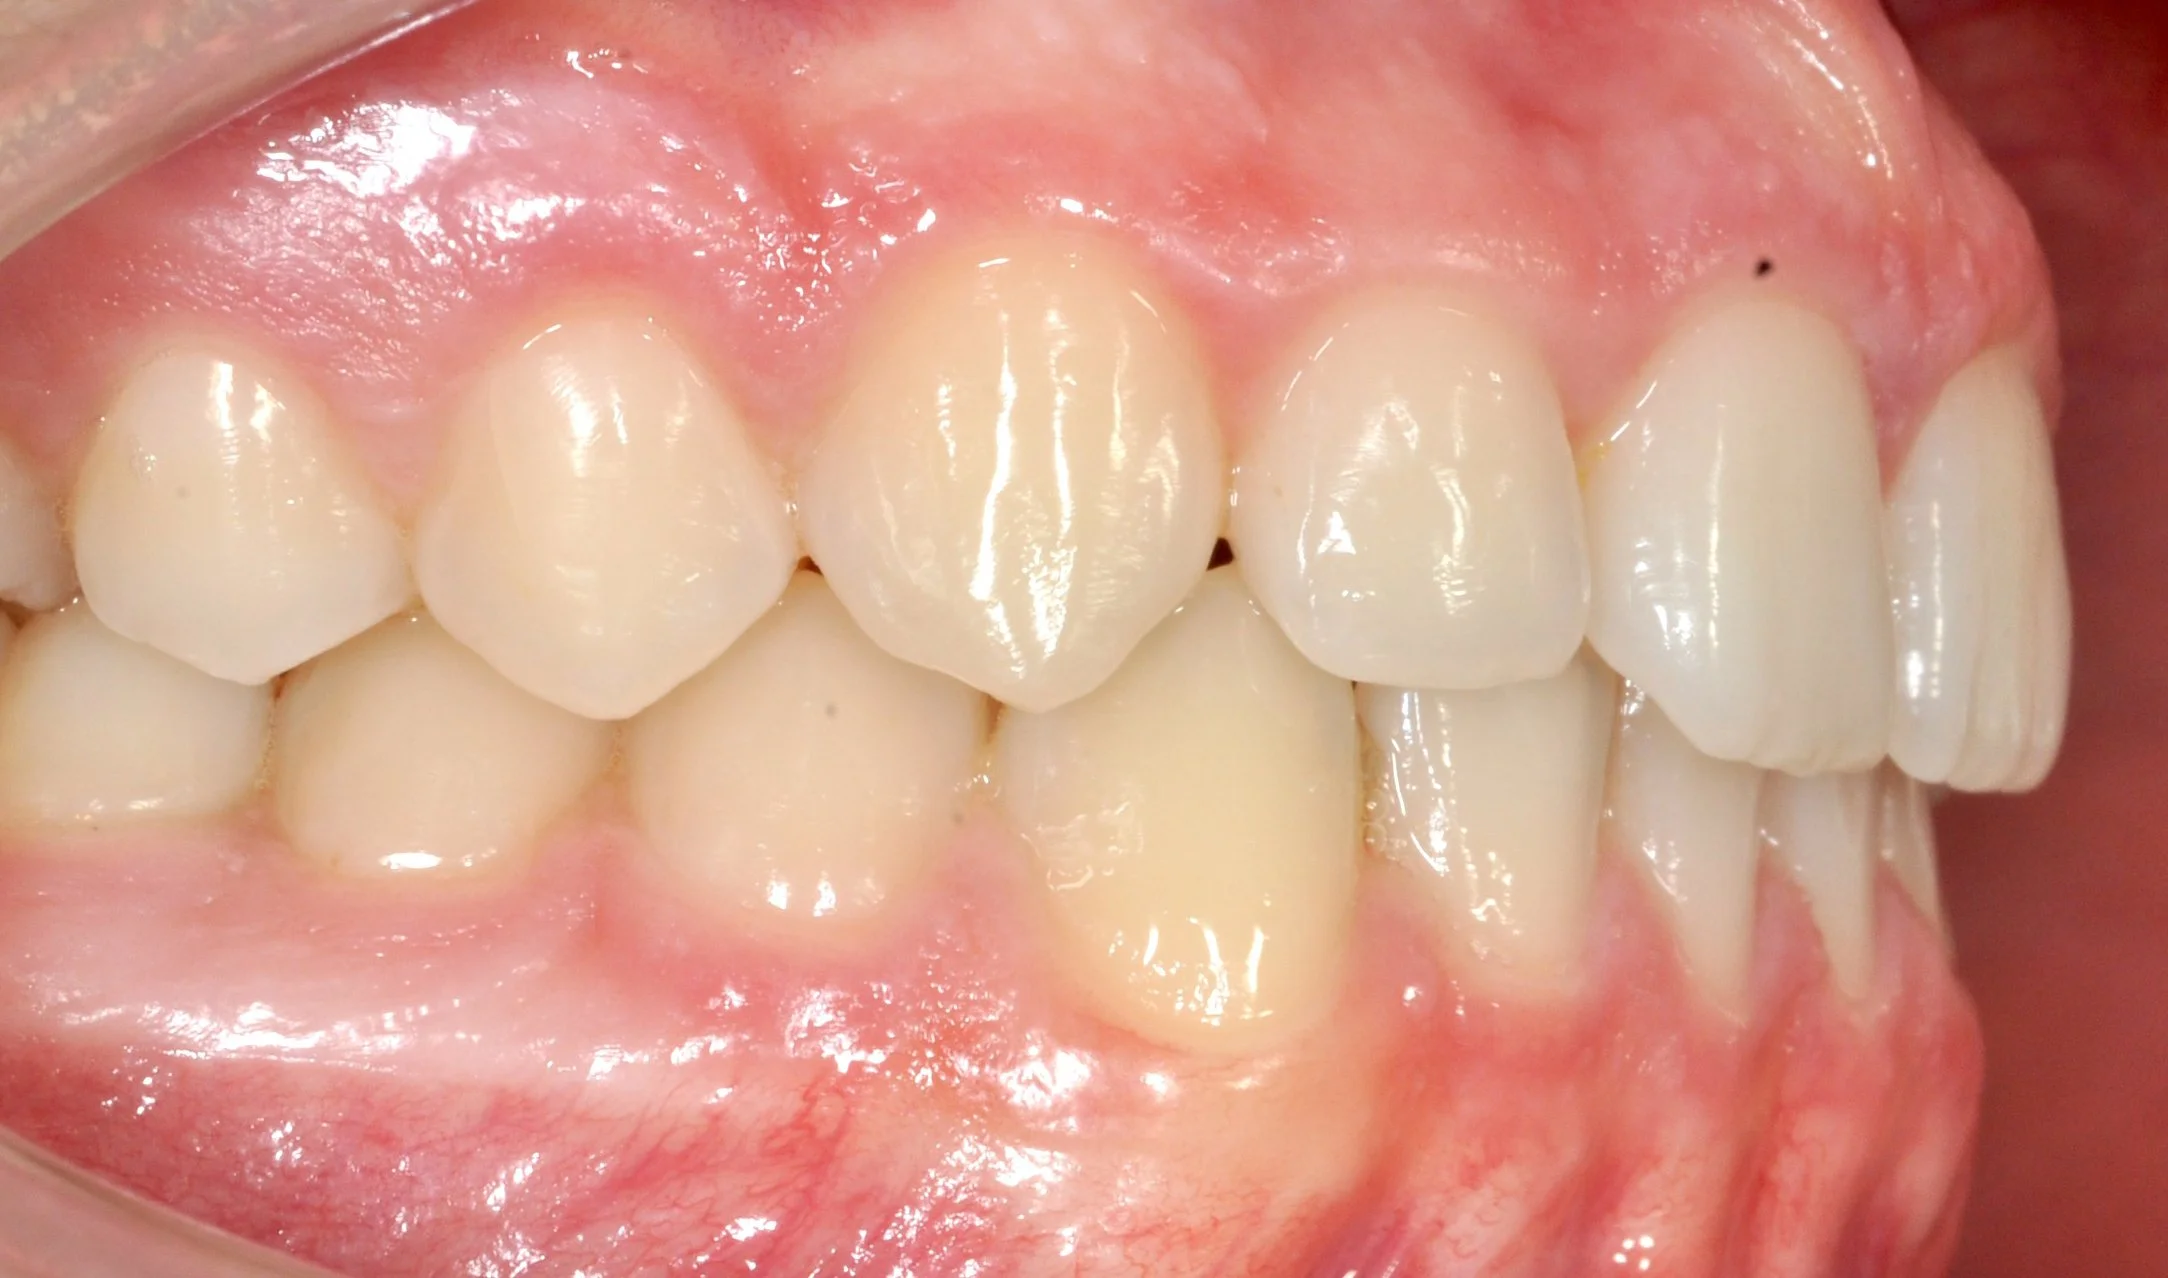

Caso 3 – Trattamento multidisciplinare in paziente adulto

Paziente adulto con incisivi malposizionati e recessioni gengivali, con esposizione della radice e disagio estetico.

Il caso è stato gestito con un approccio multidisciplinare, in stretta collaborazione con il parodontologo: prima è stata corretta la posizione dei denti mediante allineatori trasparenti, creando le condizioni ideali per la salute gengivale; successivamente le recessioni sono state trattate con un intervento mucogengivale.

Il lavoro di team ha permesso di ottenere un risultato armonioso, stabile e attento non solo all’estetica, ma soprattutto alla salute a lungo termine.

PRIMA

DOPO